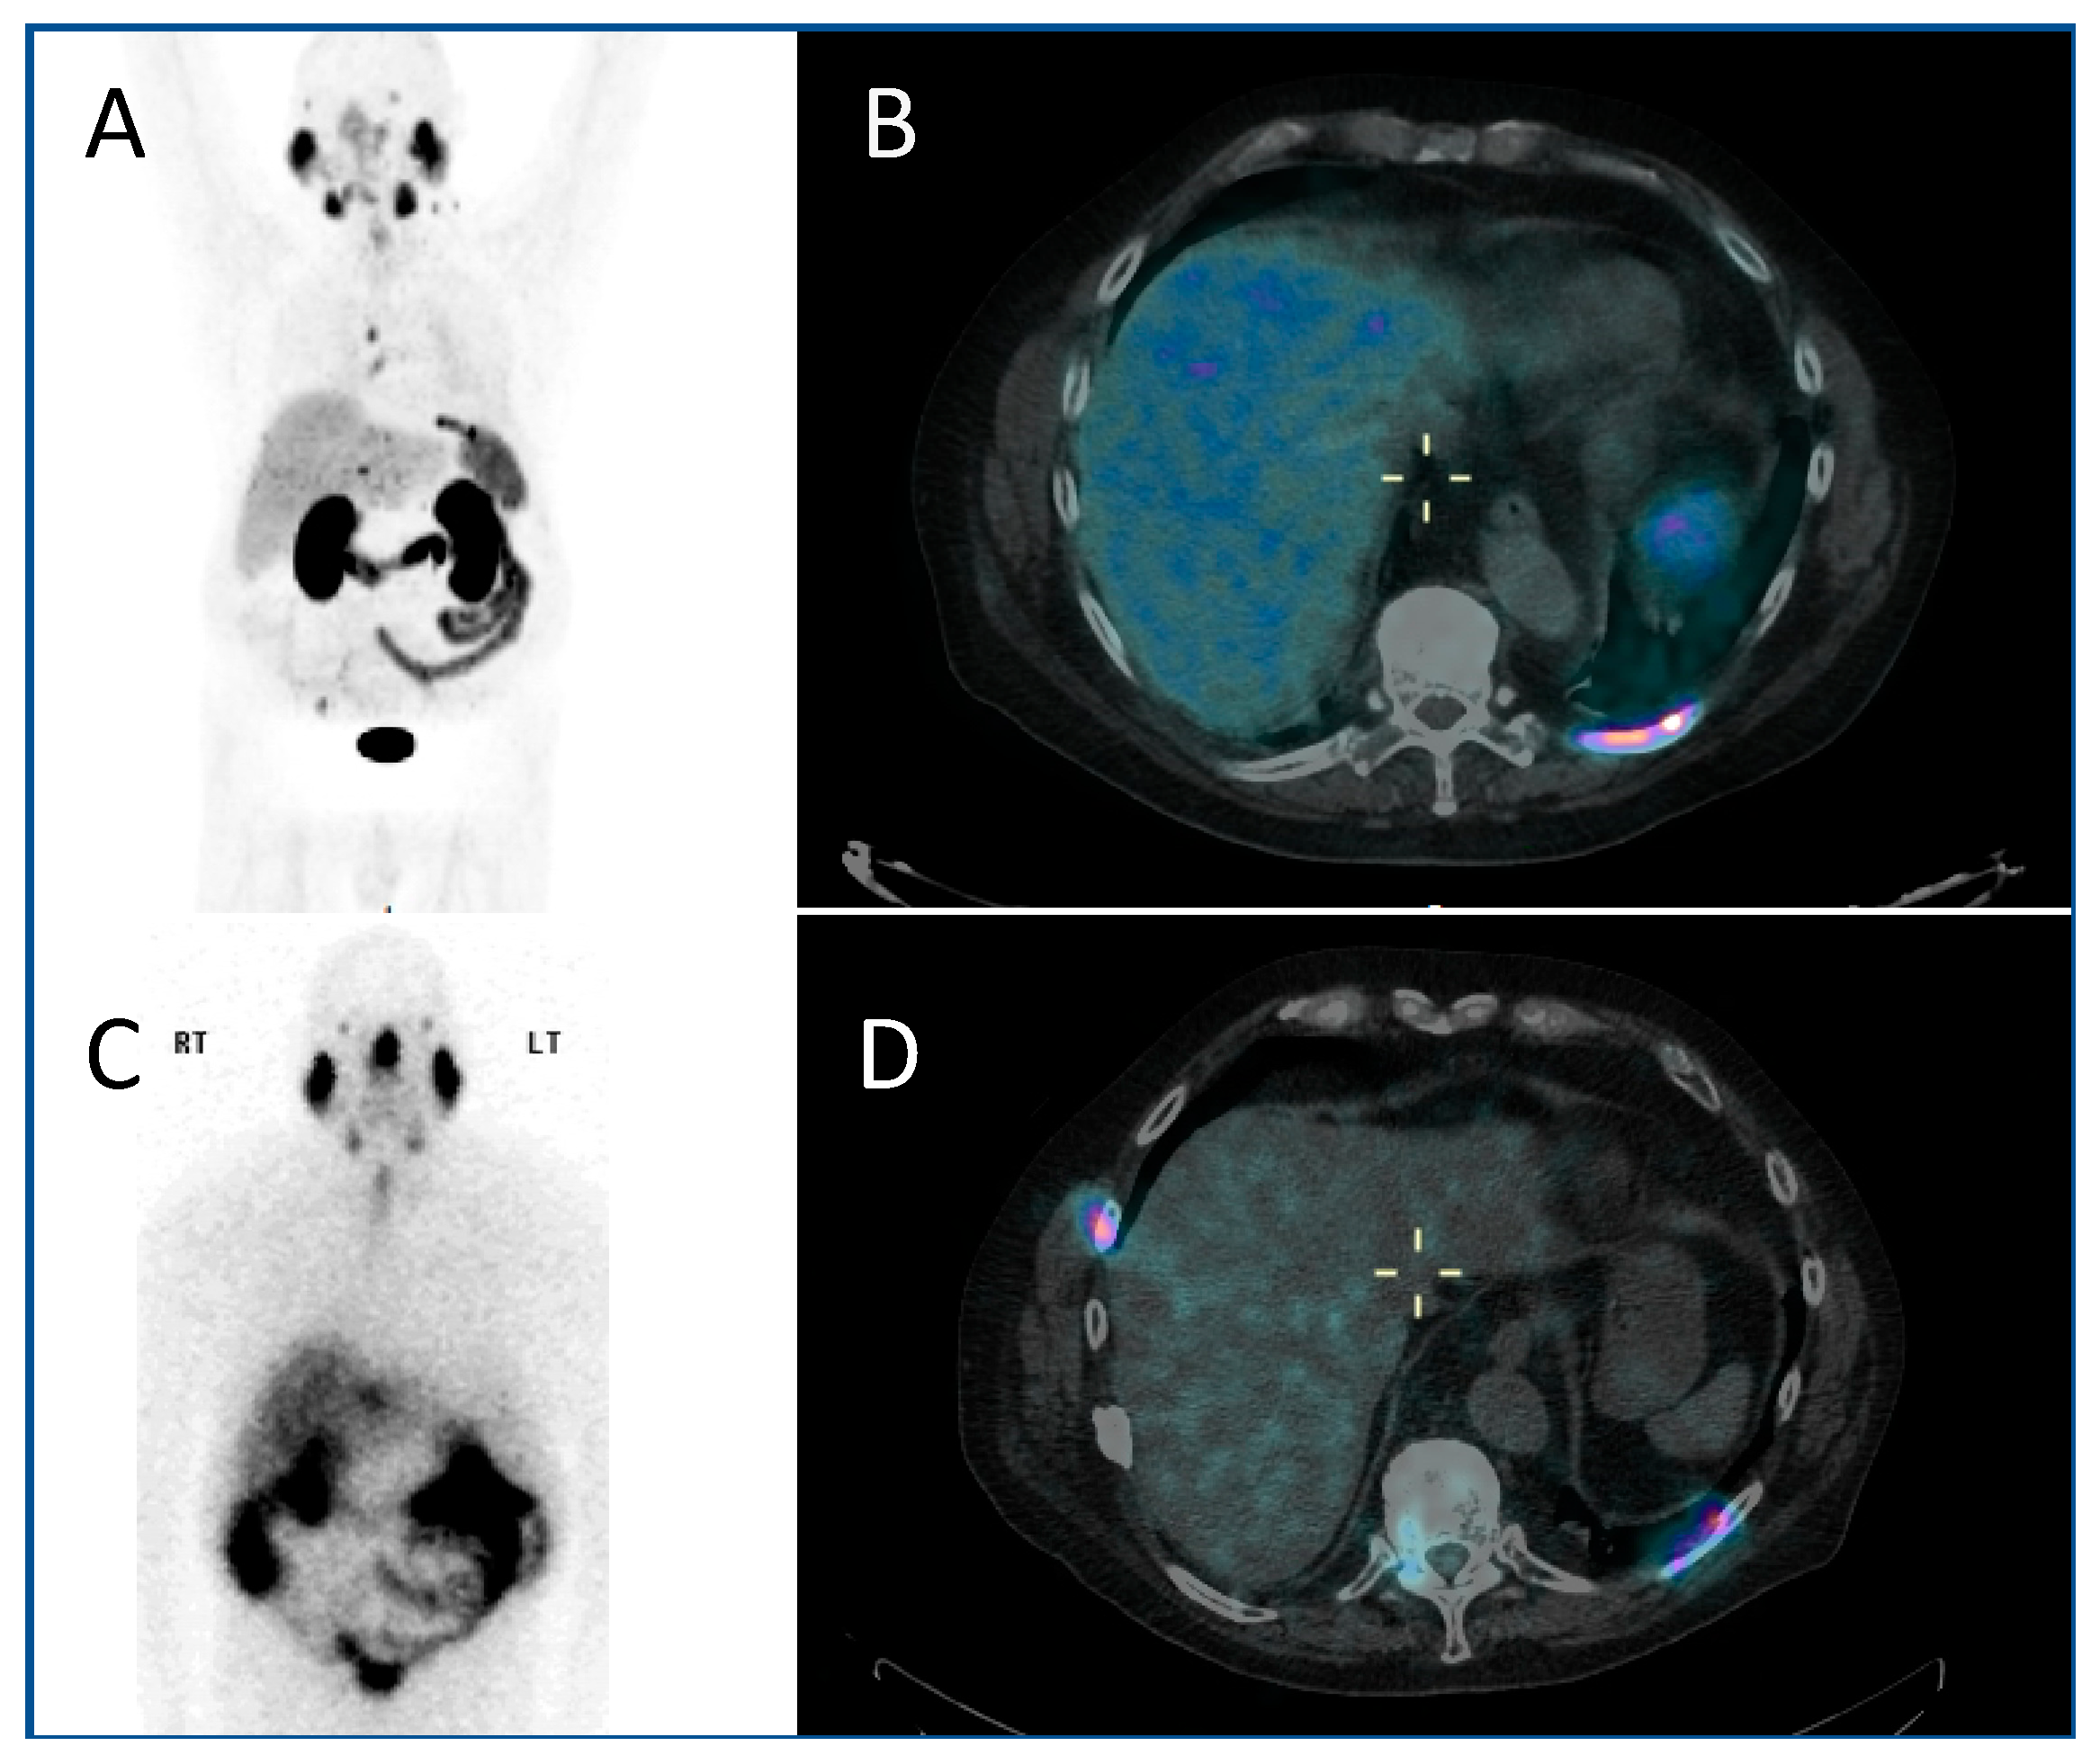

The use of PSMA (prostate-specific membrane antigen) targeted radiopharmaceuticals overcomes this, offering a more personalised treatment, targeting as it does the PSMA receptor on the cell surface of prostate cancer cells directly. Prostate-specific membrane antigen is a 750 amino acid type II transmembrane glycoprotein. It is expressed by most epithelial cells, but over-expressed (up to 1000-fold) by the majority of prostate cancer cells. Diagnostic PET imaging with 68Ga PSMA exploits the internalisation undergone by the receptor, allowing radioisotopes to be concentrated within the cell, having bound to the external component of the PSMA (Figure 2A,B). Uptake is also seen in the salivary glands, kidney and proximal small intestine. There is a correlation between the higher Gleason score of prostate cancers, castrate-resistance and PSMA expression, making the PSMA receptor an optimal target for theragnostic development [31].

Figure 2.

A PMSA-based theragnostic approach to metastatic prostate cancer. (A) Anterior view of maximum intensity projection, and (B) axial view of 68Ga-PMSA PET CT (positron emission tomography, computed tomography) demonstrating left posterior rib metastasis. Then, following 177Lu PMSA administration, (C) anterior view planar scintigraphy and (D) SPECT CT (single photon emission computed tomography, computed tomography) imaging. While these show similar appearances, post-therapy imaging has a lower resolution as the techniques are different.

The PSMA-based radiopharmaceuticals developed for therapy include 1311, 90Y and 177Lu. The side effects of all forms of PSMA-based radiopharmaceutical included dose to salivary glands and kidneys. 177Lu is a beta-emitter, with a shorter range than 90Y (1.5 mm 177Lu; 12 mm 90Y), giving it a more desirable side-effect profile. There is a good correlation between 68Ga PSMA and 177Lu PSMA distribution, allowing for pre-therapeutic dosimetric calculation to be performed in order to minimise toxicity (Figure 2C,D) [32]. 177Lu emits co-incident gamma emission, allowing post-therapeutic imaging to both confirm uptake, and allowing dosimetric calculation for subsequent therapeutic administrations [33]. 177Lu DOTA-PSMA-617 is the most extensively investigated radiopharmaceutical of this class, with its efficacy demonstrated in phase II randomised trials which showed a biochemical response in two thirds of patients. Phase III trials—TheraP and VISION—are currently underway, with completion expected in 2021 [34,35].